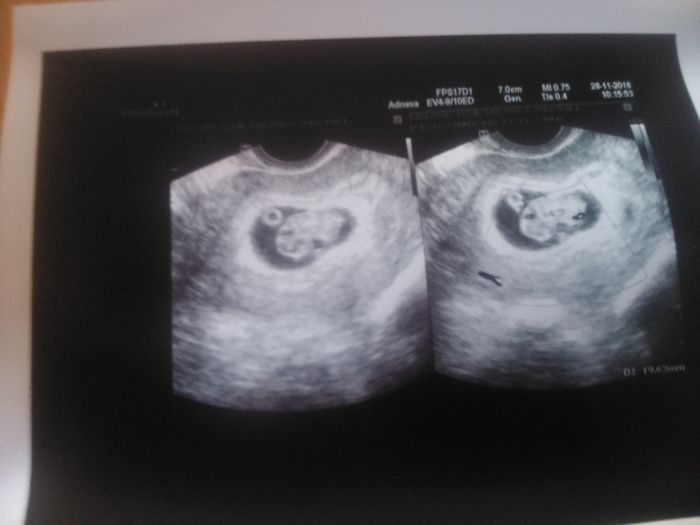

Ahojky holky, taky bych to zatim nechala jak to je. Dva dny jsem tady nebyla a je toho hodne nacteni. Chytla me strevni chripka, cely vecer az do rana jsem zvracela, jeste ze jsme byli u nasich a o Jendu se mohla postarat babicka a ja mohla v klidu lezet. Tedka byl venku s dedou a ja jeste lezim, sice to je lepsi, ale jeste to neni ono. Jinak jsem byla u doktora a vsechno je jak ma, fotka stala 50,- ale mam ji. Na dalsi kontrolu jdu 12.12. a to uz budu nosit moc a dostanu prukazku. Pokud me to pujde tak jsem fotku vlozim

Janina:krásná agnes to má 2cm? Na fotce vypadá velká

Srdíčko tluče a má jedenáct mm. Odpovídá prý přesně 7+1.

Janinko gratuluji ke krásné fotce. Taky už mám jednu doma z dneška, ale nejde mi to vkládat no. Tak to je jedno :-).

Holky diky. Ano ma 2 cm, Agnes se me taky libi ale manzel chce Emu. Kluka si nepripoustime, bude holka :-)